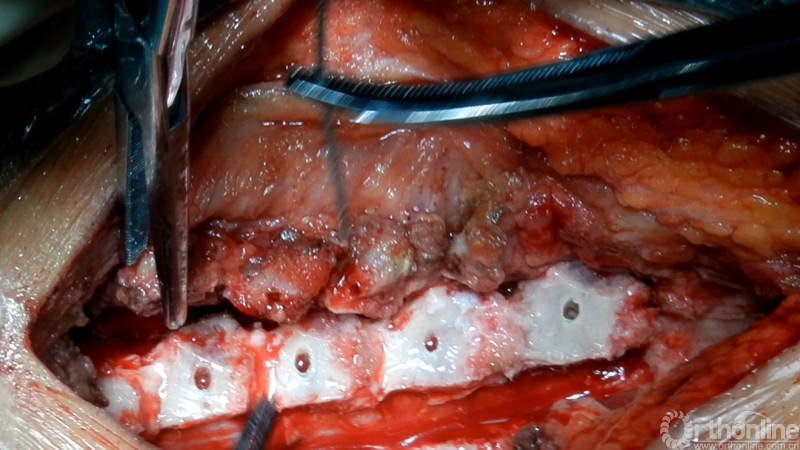

超声骨刀开门

重建颈半棘肌

椎旁肌点对点缝合